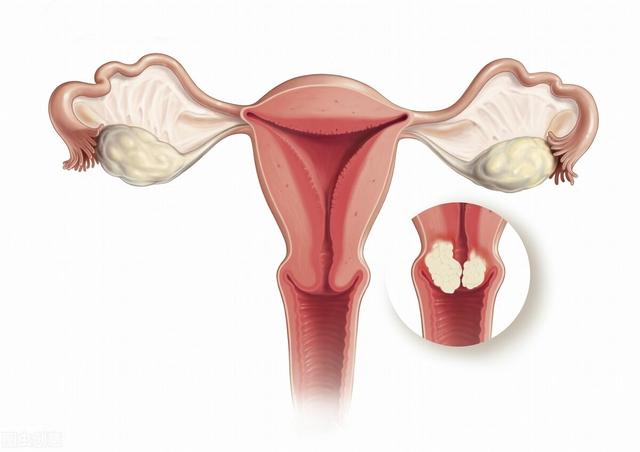

3.子宮頸部びらん

また、子宮頸部上皮細胞が異型過形成(子宮頸部上皮内新形成とも呼ばれる)を起こしていることが判明した場合は、細胞変異の程度を注意深く観察する必要がある。子宮頸部の炎症は、多くの場合、子宮頸がんにつながる可能性のある遺伝的変化を子宮頸部上皮に引き起こす危険性の高いHPV感染の結果である。

子宮頸部上皮内新生物→子宮頸がん

子宮頸部上皮細胞は、HPVに持続感染すると、異型過形成から癌化する可能性があり、その期間は最長で10年以上にも及ぶ。

中でも子宮頸部上皮内新形成は、一般に子宮頸部前癌病変とも呼ばれ、3つのグレードに分けられ、グレードが高いほど癌化しやすく、グレードが低いほど治療に適している。

一人だ、性的に活発な女性は、年に一度はTCTとHPV検査を受けるべきです。異常があれば、コルポスコピーまたは生検が必要です。

二、慢性子宮頸管炎と子宮頸部前癌病変を積極的に治療すること。性生活は衛生的でなければならない。

三、子宮頸がんワクチン接種は、子宮頸がんの発症を予防するために、条件が許せば受けることができる。

4人だ、悪い習慣は身体の免疫力を低下させ、ウイルス侵入の機会を作り出す。

4.子宮頸部円柱上皮外反症:以前は子宮頸部びらんとも呼ばれていた。子宮頸部円柱上皮外反症は、性交渉、人工妊娠中絶、出産、感染症、外科手術などによって引き起こされ、扁平上皮の代わりに外傷を覆うように子宮頸部円柱上皮過形成を引き起こし、慢性子宮頸管炎の局所の特徴の一つであり、子宮頸癌を誘発する可能性があります。また、子宮頸癌の発生にはヒトパピローマウイルス(HPV)感染が関係しており、ハイリスクHPV感染者の中には、子宮頸部の扁平上皮-柱状上皮接合部に持続感染している場合、前癌病変や子宮頸癌が発生しやすい人がいる。

- 子宮頸部内新形成(CIN)は子宮頸癌の前癌病変であり、ヒトパピローマウイルス感染と関連している。HPVとして知られるヒトパピローマウイルスには全部で120種類以上の型があり、そのうち10種類以上が子宮頸がんの発症に深く関係している。HPV感染は子宮頸癌の99%に認められ、そのうち約70%はHPV16型とHP V18型に関連している。子宮頸部内膜症(CIN)はグレードI、II、IIIに分類され、グレードIIIではすでにin situ子宮頸がんと同等である。HPV感染に対する特異的な薬剤はない。定期的なHPV+細胞診は子宮頸がんの早期発見につながる。 HPV感染はワクチン接種で予防できる。クリニックでは、子宮頸がんの80%以上を予防できる国産品と輸入品の両方を用意している。

何年か前に、人々は個人の衛生などに注意しないため、男性はあまり入浴しない、桂皮頭粘膜長期分泌、炎症刺激、粘膜異型過形成、最終的に癌、現在このような状況はまれですが、男女の混沌とした生活などの理由で、女性の子宮セリアック病が多く発生し、子宮頸癌の症状と子宮頸セリアック病のパフォーマンスが非常に似ているので、非常に見落とされやすく、特に警戒する必要があります。